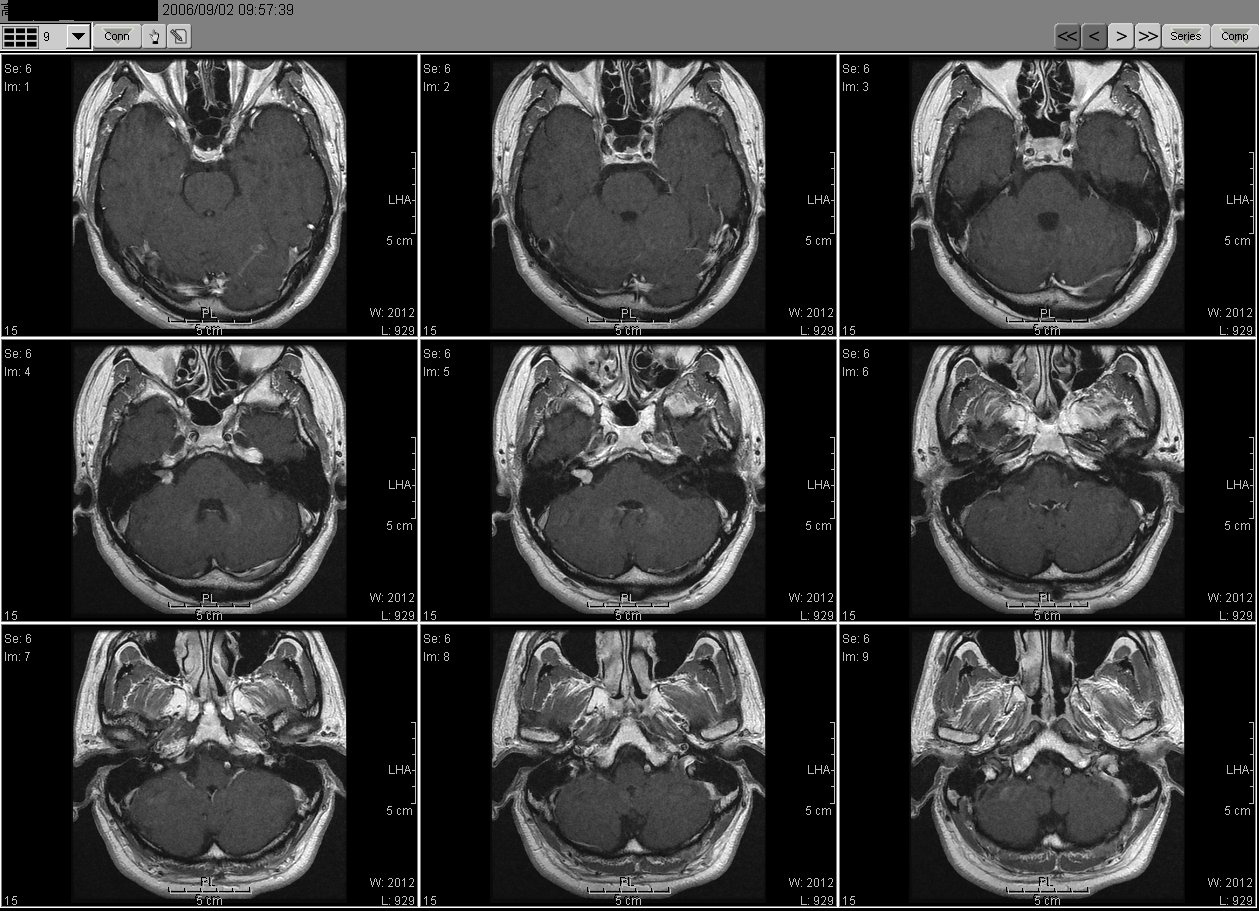

2006_09_02 MRI

2006_09_02MRI01